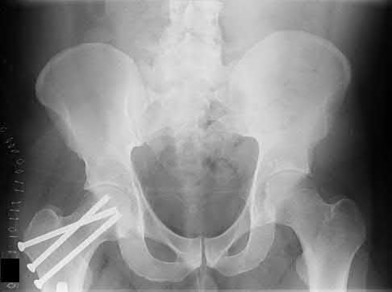

1026) Figures A and B show the six-month follow-up radiographs of a 62-year-old woman who sustained a hip fracture in a fall. Prior to the fall, the patient was active and had no difficulty with ambulation. The patient underwent open reduction and internal fixation with a sliding hip screw device. She has difficulty with ambulation, continues to walk with a walker, and reports startup pain. What is the most appropriate management at this time?

5. Conversion to total hip arthroplasty with a primary tapered stem Corrent answer: 4

The radiographs demonstrate a healed fracture with penetration of the screw through the femoral head into the acetabulum as well as osteonecrosis and collapse of the femoral head (Figure 129b). Conversion to total hip arthroplasty with a long stem is necessary to bypass the femoral cortical defects from the screw holes. A primary tapered stem is not appropriate because of the proximal femoral deformity and the stress risers associated with the screw holes. Removal of hardware, valgus osteotomy, and revision of the internal fixation are not appropriate in the presence of the femoral head collapse and acetabular penetration.